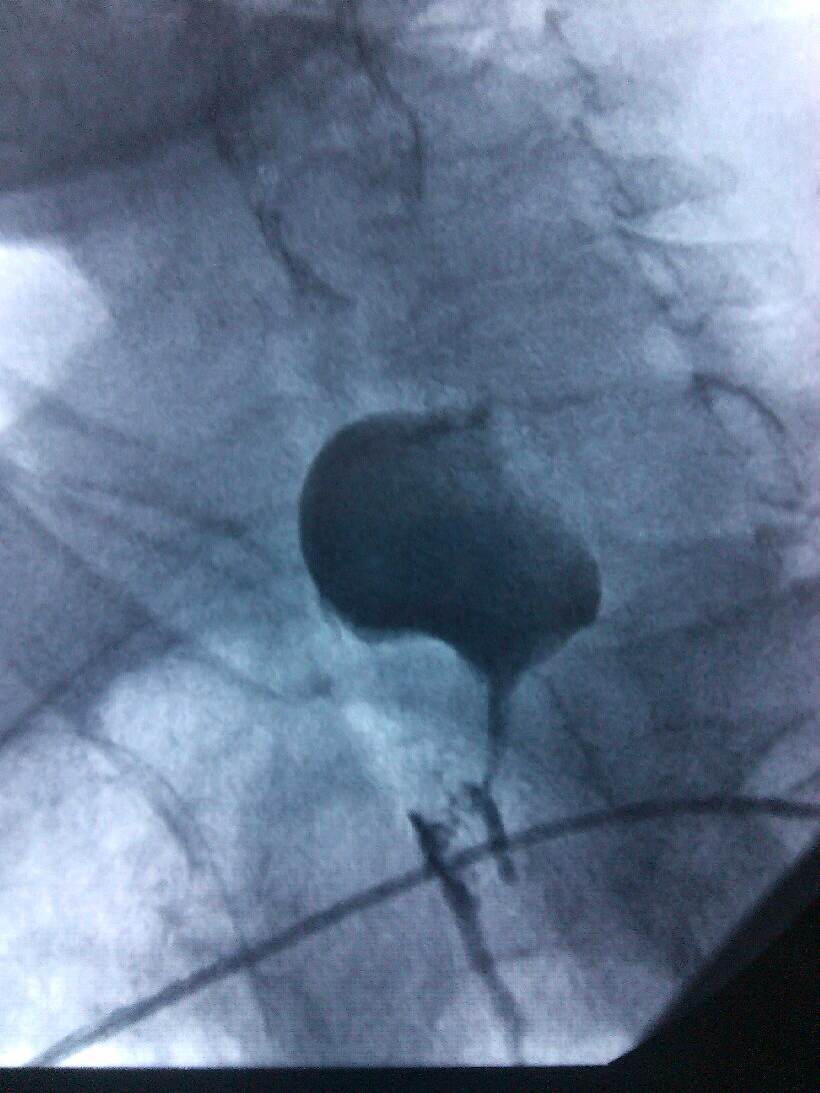

根据病人的的身体条件,无法采用手术、放疗、化疗进行治疗。肿瘤科主任、副主任医师熊小平组织医生详细分析患者的病情,找到病因所在,制定周密的治疗方案,运用食管支架植入法将食管扩张,这样既解决了患者的“吃饭”问题,又解决了分泌物排流的问题,减轻了患者的痛苦,提高了生活质量。患者及家属非常感激,多次口头表示感谢:“没想到91club